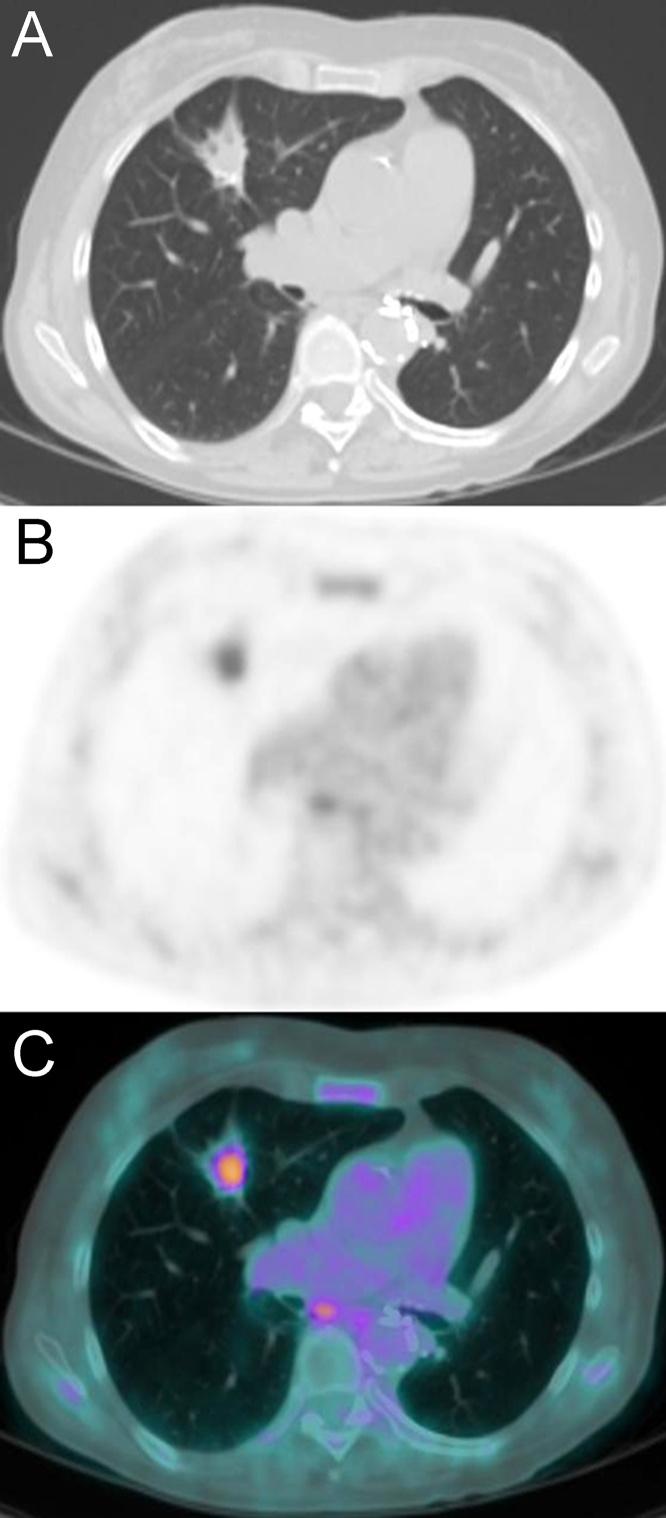

Persistent pure ground-glass nodules (pGGNs) typically show an indolent course with very slow growth rates. These slow-growing lesions exhibit different growth patterns regardless of their initial computed tomography (CT) features. Therefore, predicting the aggressive behavior of pGGNs on initial CT remains a diagnostic challenge. The literature reports that computerized analysis and various quantitative features have been tested to improve the risk stratification for pGGNs. The present article describes the long-term follow-up of two pGGNs with different behavior and introduces, for the first time, a new computerized method of analysis that could be helpful for predicting the future behavior of pGGNs.

持续性纯磨玻璃结节(pGGN)通常病程进展缓慢,生长速度极慢。这些生长缓慢的病变无论其初始计算机断层扫描(CT)特征如何,都表现出不同的生长模式。因此,在初始CT上预测pGGN的侵袭性行为仍然是一项诊断挑战。文献报道,已经对计算机分析和各种定量特征进行了测试,以改善pGGN的风险分层。本文描述了两个具有不同行为的pGGN的长期随访情况,并首次介绍了一种新的计算机分析方法,该方法可能有助于预测pGGN的未来行为。